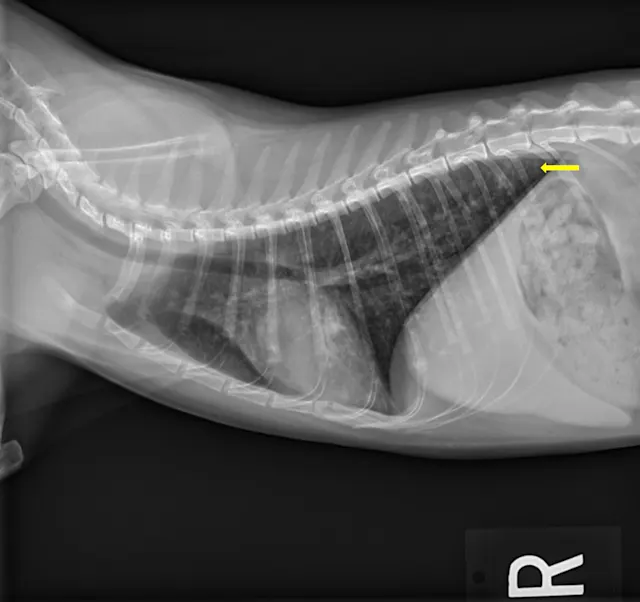

At the 2-month recheck, continued clinical improvement was observed. The owner reported Eleanor was doing well at home. Her body weight had increased to 8.3 lb (3.8 kg); BCS was 4/9.On physical examination, mildly increased bronchovesicular sounds were still present. Fundic examination results were normal. Thoracic radiographs showed continued improvement; remaining lesions were predominantly in the peripheral lung field with a more caudodorsal distribution (Figure 3).

FIGURE 3 Left lateral (A), right lateral (B), and ventrodorsal (C) thoracic radiographs 2 months after initiation of itraconazole. Remaining lesions (arrows) were predominantly in the peripheral lung field with a more caudodorsal distribution.